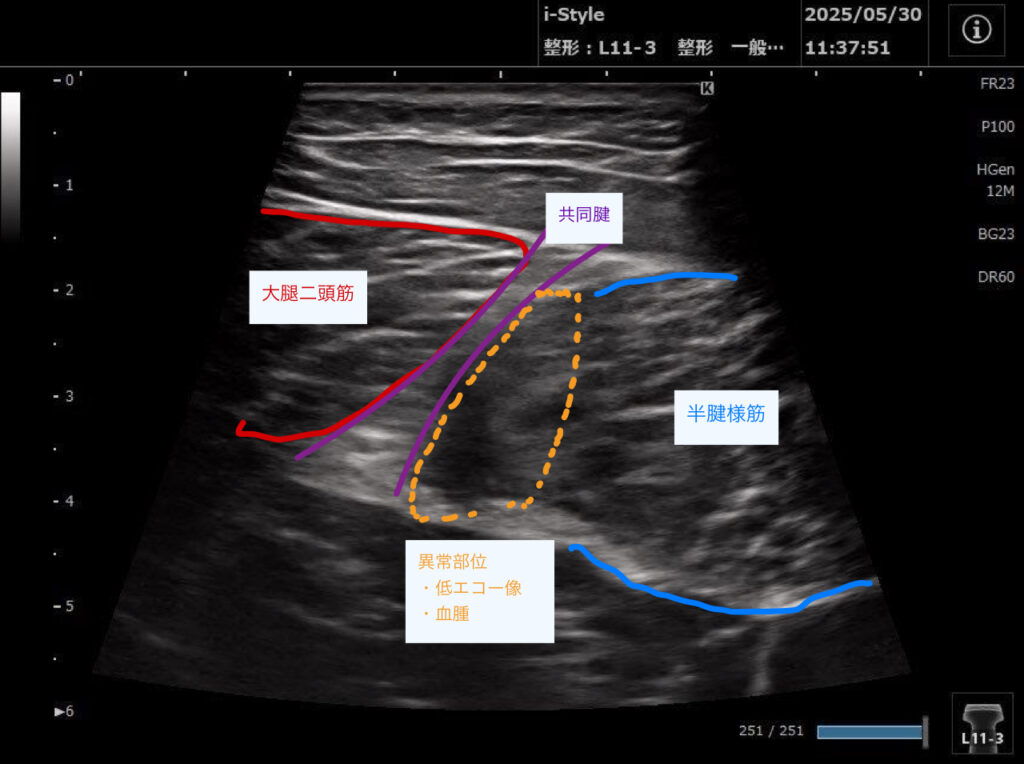

・超音波エコーで観察した結果、ハムストリングの筋が重なっている部分(共同腱)の収縮の低下があり、半腱様筋周囲に血種の低エコー像を認めた。

2回目以降:歩行や日常生活での痛みはさらに改善した。超音波エコーでの観察は毎回行い、血腫の吸収具合を確認し筋肉や神経の癒着を改善していった。

スポーツ復帰のタイミングは痛みのありなしでの判断ではなく、毎回超音波エコーで確認を行い、しっかりと筋収縮が行えることを確認できた、8週間後となった。